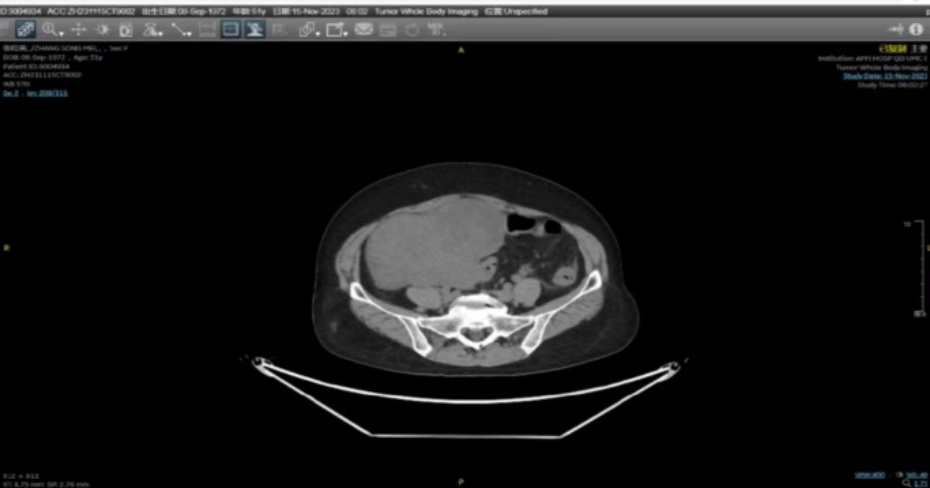

入院行妇科查体:子宫前位增大如孕3月大,质中,活动可,无压痛,右侧附件区扪及直径约15 cm肿物,有压痛,左侧附件区可扪及直径约6 cm肿物,有压痛,余未扪及明显异常。患者入院后完善相关辅助检查:实验室检查:血清肿瘤标记物:SCC:1.11 ng/mL,NSE:11.80 ng/mL,CA153:114.00 U/mL,CA 724:<1.50 U/mL胃泌素释放肽前体22.12 pg/mL;肝功:谷丙转氨酶35 U/L,谷草转氨酶37U/L;HPV:16型阳性;血常规、血凝常规、肾功、电解质检测等实验室检查未见明显异常。影像学检查:妇科超声:子宫肌层内见多个低回声结节,大者:前壁5.1 × 4.9 × 4.1 cm (外突),左侧壁6.4 × 6.3 × 5.6 cm (外突,推压内膜),右侧壁下段5.5 × 4.1 × 4.4 cm (明显推压内膜),盆腔偏右见14.7 × 11.8 × 8.1 cm、偏左见6.3 × 6.0 × 3.8 cm低回声团,形态欠规则,局部边界欠清,CDFI:内见点条状血流信号,腹盆腔内见液性暗区,腹腔较深处约2.8 cm,盆腔较深处约3.3 cm,透声可;PET-CT:1) 腹腔-盆腔内见2处不规则软组织密度肿块,内见低密度区,与双侧附件、部分肠管关系密切,不均匀代谢增高,SUVmax约4.8 (图1(a)图1(b));腹、盆腔积液;考虑肿瘤,附件或肠道来源可能性大,建议获得病理学诊断;2) ① 左肺下叶内前基底段磨玻璃密度结节,边界清,代谢略高于肺本底,SUVmax约1.0,不除外早期肺肿瘤,建议胸外科会诊;② 双肺数个小结节,未见异常代谢,建议CT随诊;③ 双肺慢性炎症;④ 右侧胸腔积液(少量);3) 左乳癌术后所见,局部未见复发征象;4) ① 左肾结石;② 子宫肌瘤;心脏超声:室间隔心肌肥厚(基底段),左室舒张功能减低;因HPV高危型阳性遂行宫颈活检病理:粘膜组织慢性炎,部分复鳞上皮呈低级别上皮内病变(LSIL/挖空细胞);下肢血管超声未见明显异常。

患有乳腺癌的女性与一般人群相比,发生恶性卵巢病变的风险增加。因此,尽管患者仍然没有症状,但进行腹盆腔定期检查很重要。如果有怀疑盆腔肿物的影像图像,伴CA125升高,应进行手术评估[4]。该患者术前PET-CT提示:腹腔–盆腔内2处不规则软组织密度肿块,内见低密度区,与双侧附件、部分肠管关系密切,不均匀代谢增高,SUVmax约4.8;腹、盆腔积液;考虑肿瘤,附件或肠道来源可能性大。结合既往病史,考虑该肿瘤倾向于卵巢来源可能性大,遂行全麻下开腹探查术,术中证实该肿瘤为卵巢来源且术后病理为乳腺浸润性小叶癌转移。